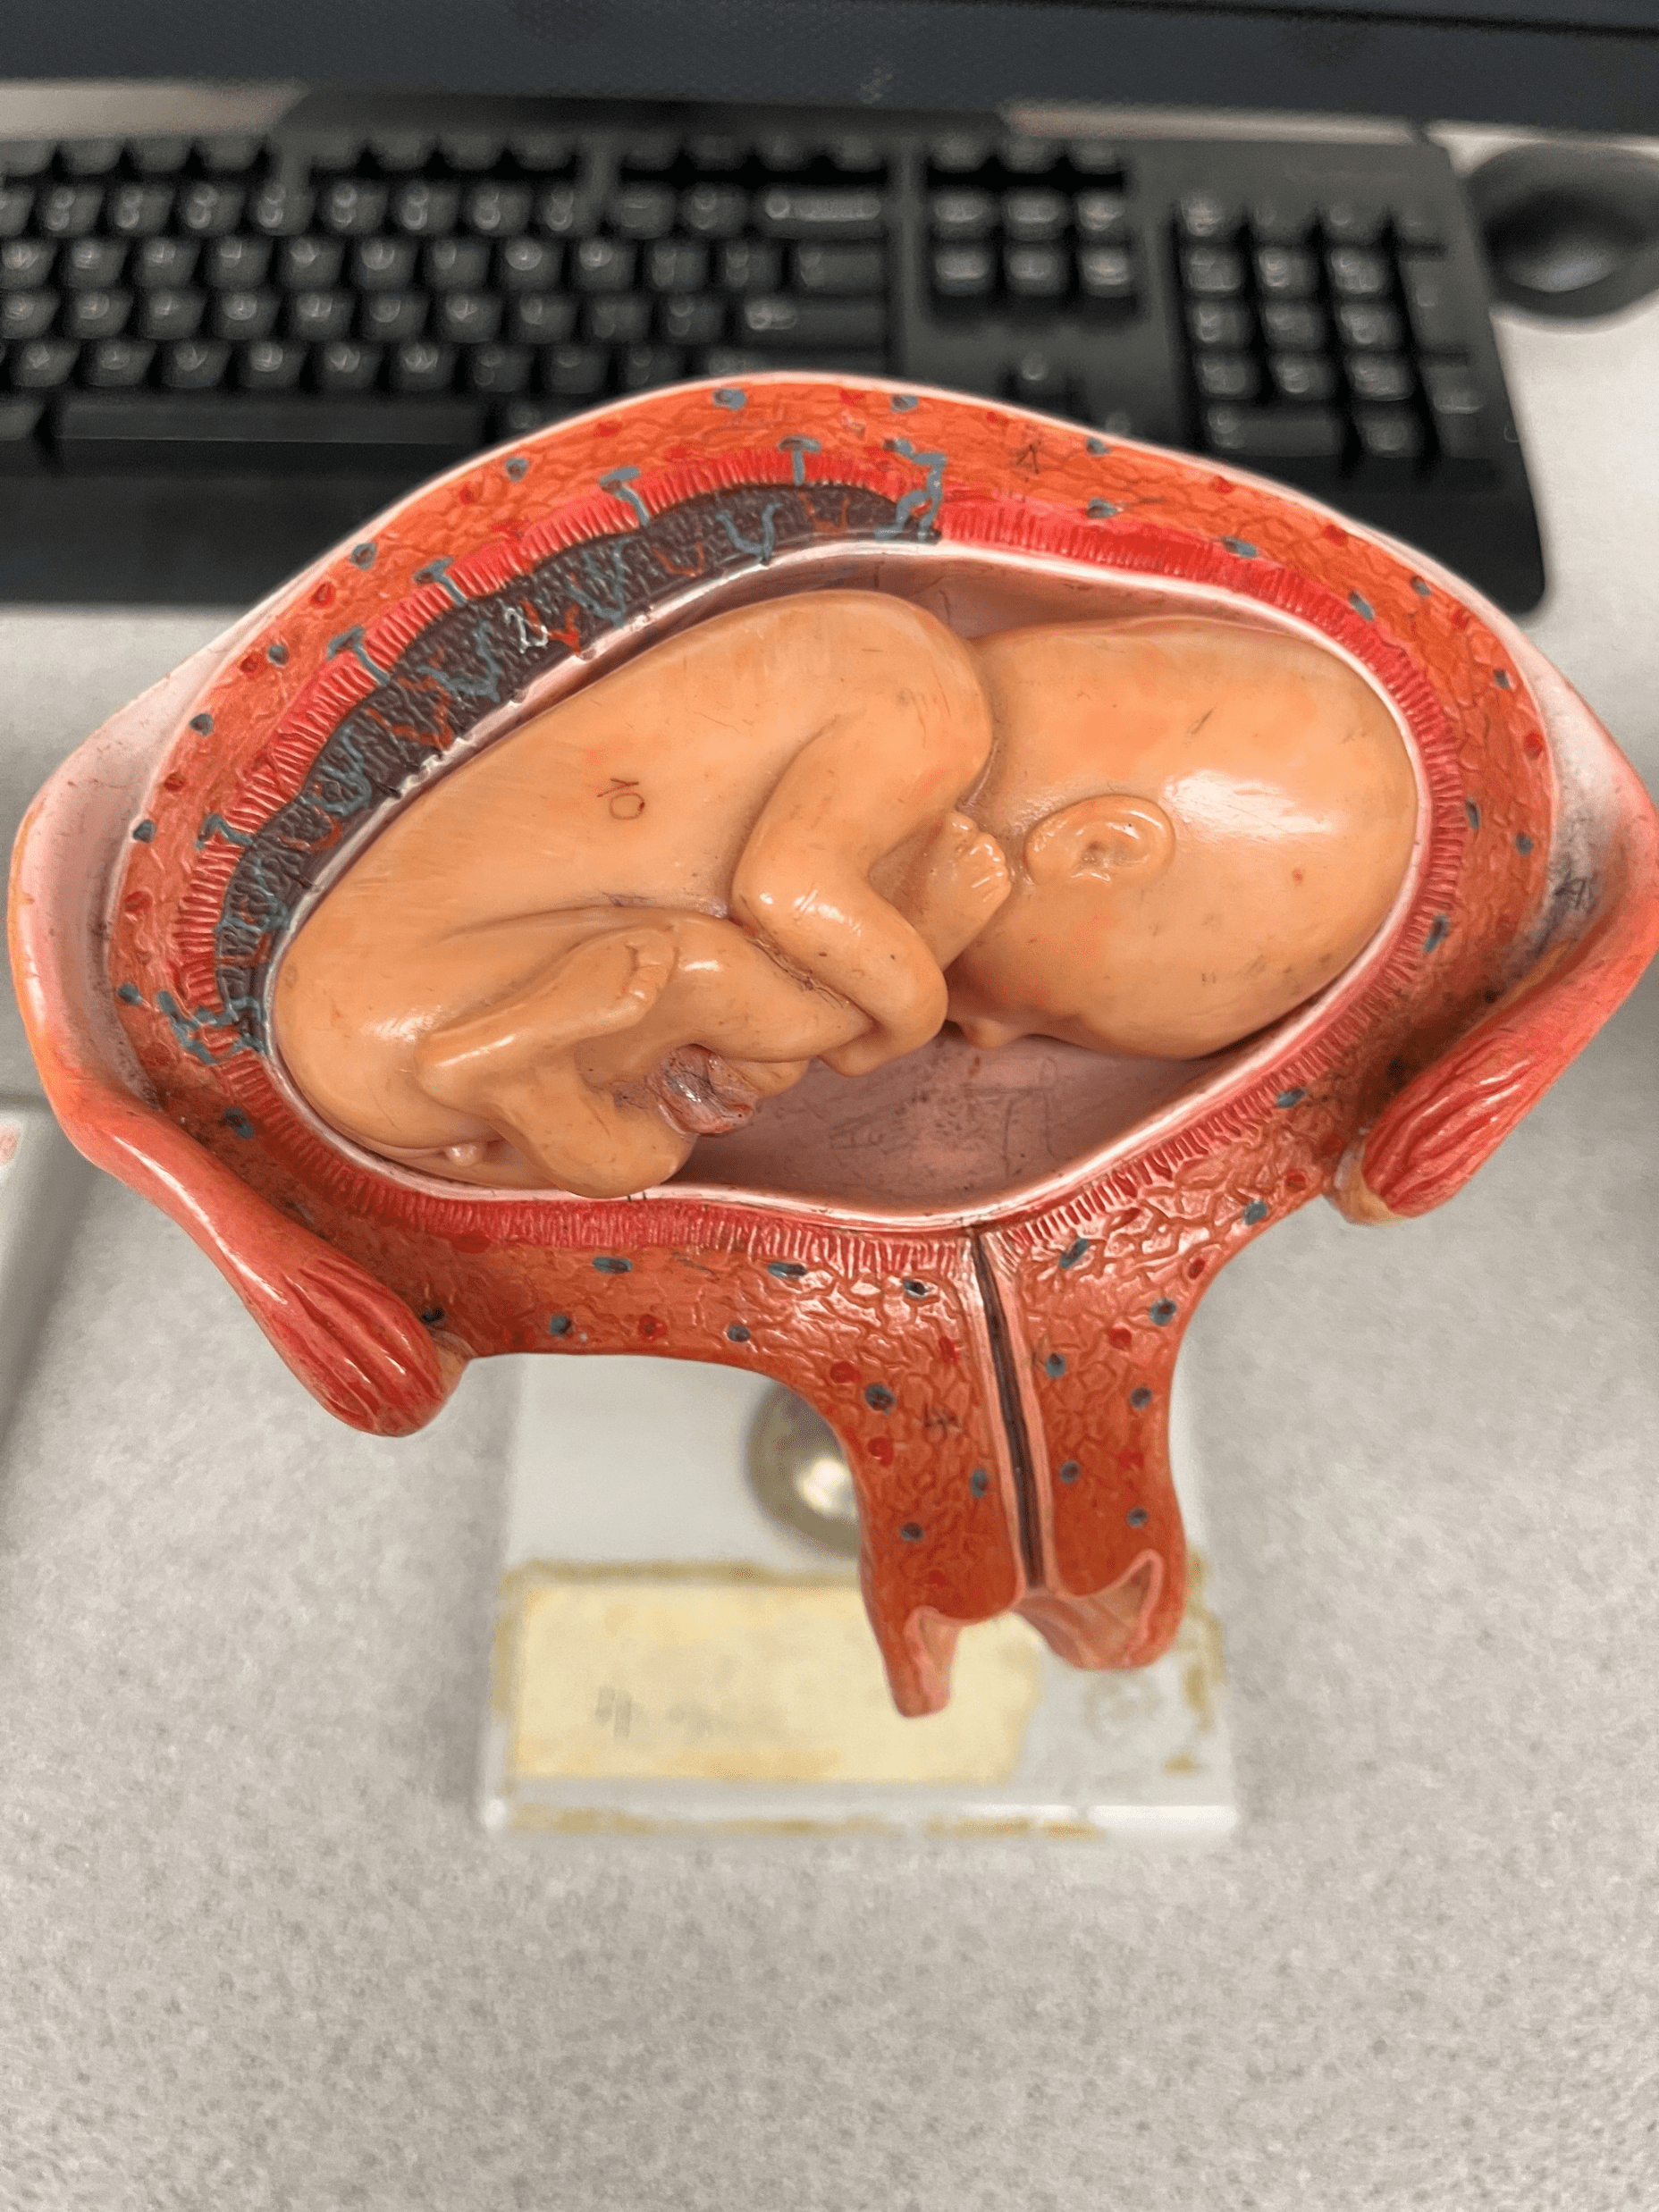

• Model of the developing fetus in the uterus.

• The position in which the fetus faces downwards.

• Model of the developing fetus in the uterus.

• The position in which the feet face downwards.

• Model of the developing fetus in the uterus.

• The position in which the fetus faces upwards.

• Also known as the supine position.

• Model of the developing fetus in the uterus.

• The position in which the head faces downwards.

• Also known as the vertex position.